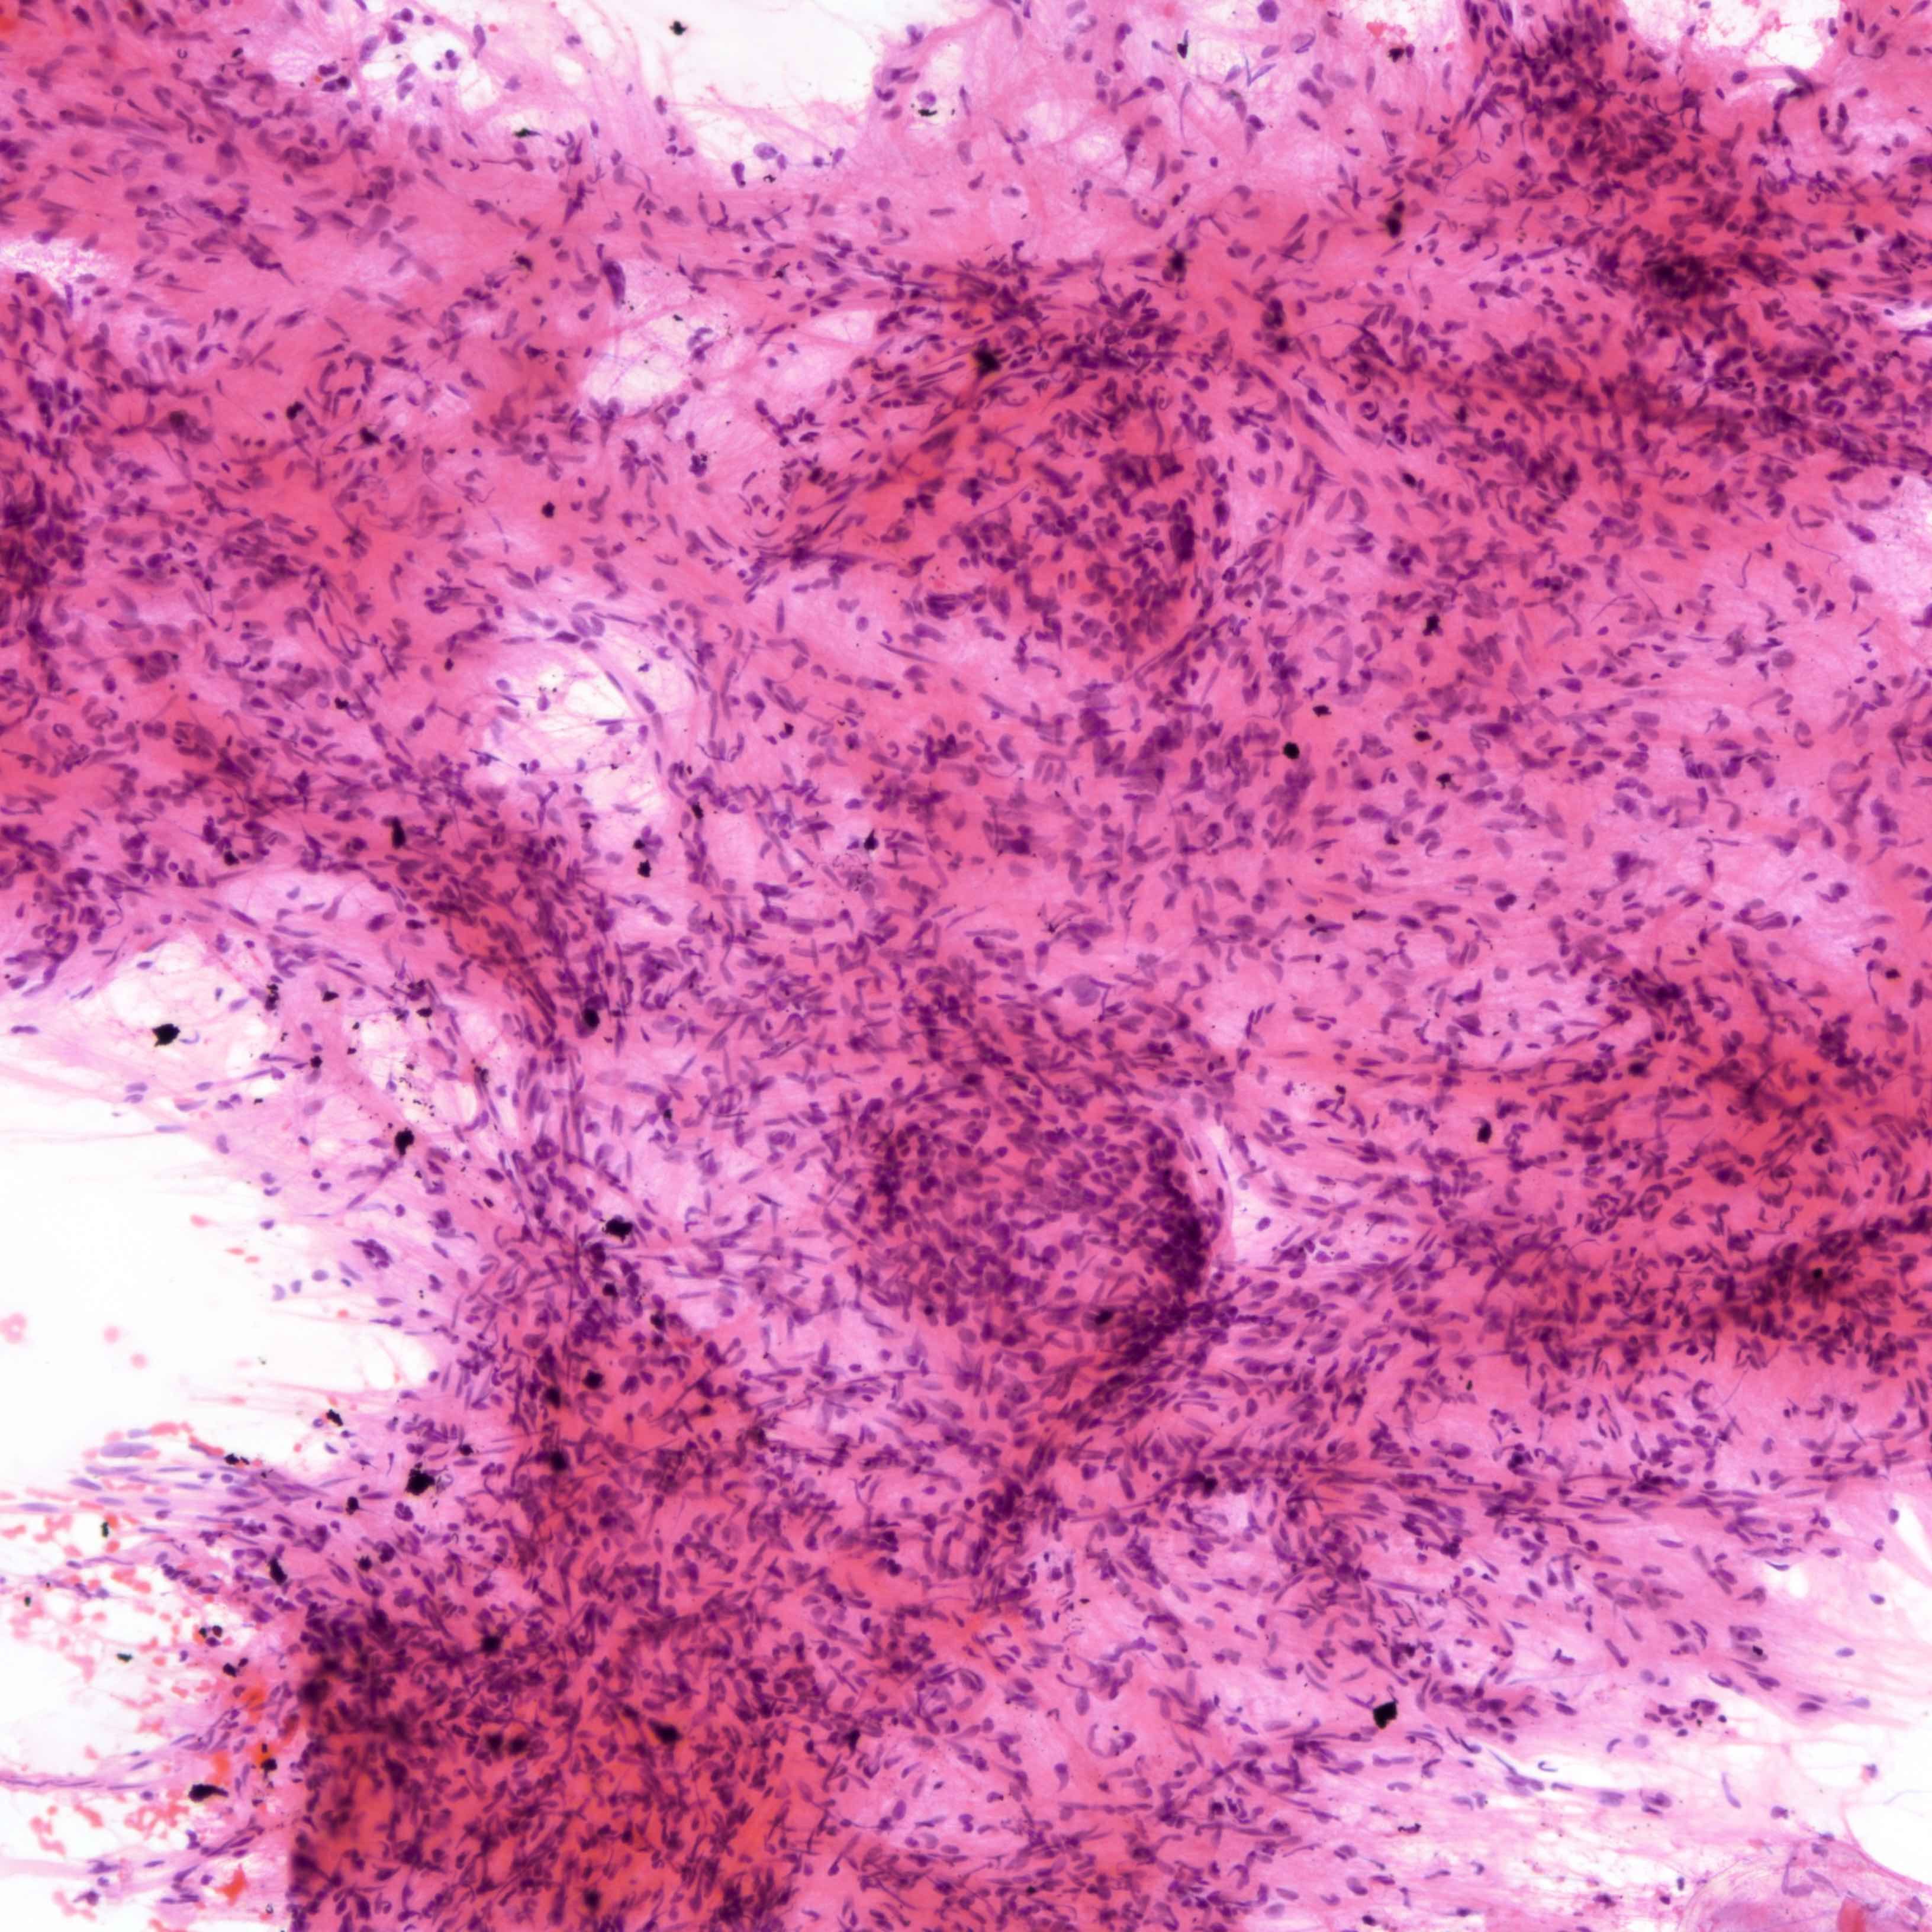

Cytology description

- Fibromyxoid stromal clumps

- Reduced epithelial stromal ratio compared with fibroadenomas

- Higher nuclear atypia and cellularity in phyllodes tumor of higher grades

- Large wavy and folded epithelial clusters

- Usually exhibits benign cytomorphology

- Occasionally, hyperplastic changes with enlarged and vesicular nuclei and small visible nucleoli may be seen

- Fibroblastic pavements

- Increased atypia in dispersed cells in phyllodes tumor of higher grades (Cancer Cytopathol 2010;118:33)

- Multinucleated tumor cells and marked stromal anaplasia reported in malignant phyllodes tumor (Cancer Cytopathol 2010;118:33)

Cytology images

Contributed by Joshua J.X. Li, M.B.Ch.B. and Gary M. Tse, M.B.B.S.

Malignant phyllodes tumor